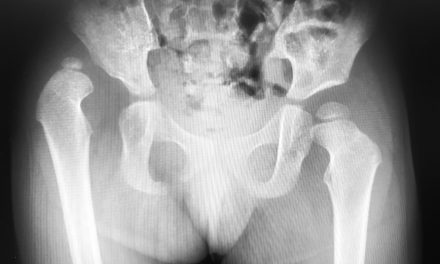

Sve kosti u koštanom sustavu služe mnogim raznim funkcijama koje su važne za naše tijelo - od davanja tjelesne podrške do omogućavanja normalnog kretanja. Osim navedenog, one također imaju važnu ulogu u proizvodnji naših krvnih stanica te skladištenju masti. Što je koštana srž? Riječ je o spužvastom/viskoznom tkivu koje ispunjava unutrašnjost naših kostiju. Razlikujemo dvije koštane srži: Crvena koja pomaže u stvaranju novih krvnih stanica i žuta koja pomaže u skladištenju dodatnih masti. Koje funkcije ima koštana srž? Crvena je uključena u hematopoezu, ili stvaranu novih krvnih stanica. Matične stanice koje se nalaze u ovoj srži mogu se razviti iz mnogih krvnih stanica:

Crvene krvne stanice - Prenose krv koja je bogata kisikom do svake stanice. Trombociti - Pomažu kod procesa zgrušavanja krvi i tako se eliminira nekontrolirano krvarenje. Bijele krvne stanice - Pomažu u borbi protiv infekcija. Kako starimo, crvena srž se zamjenjuje sa žutom i možemo ju pronaći jedino u: Lubanji, kralježnici, sternumu, rebrima, kostima nadlaktice, krajevima bedrenih kostiju, potkoljenicama. Žuta je uključena u proces skladištenja masti koja može poslužiti kao dodatni oblik energije. Ona također ima i mezenhimske matične stanice koje se mogu razviti od kostiju, masti, hrskavica ili mišića. Većina kostiju u našem tijelu sadrži žuti oblik srži.